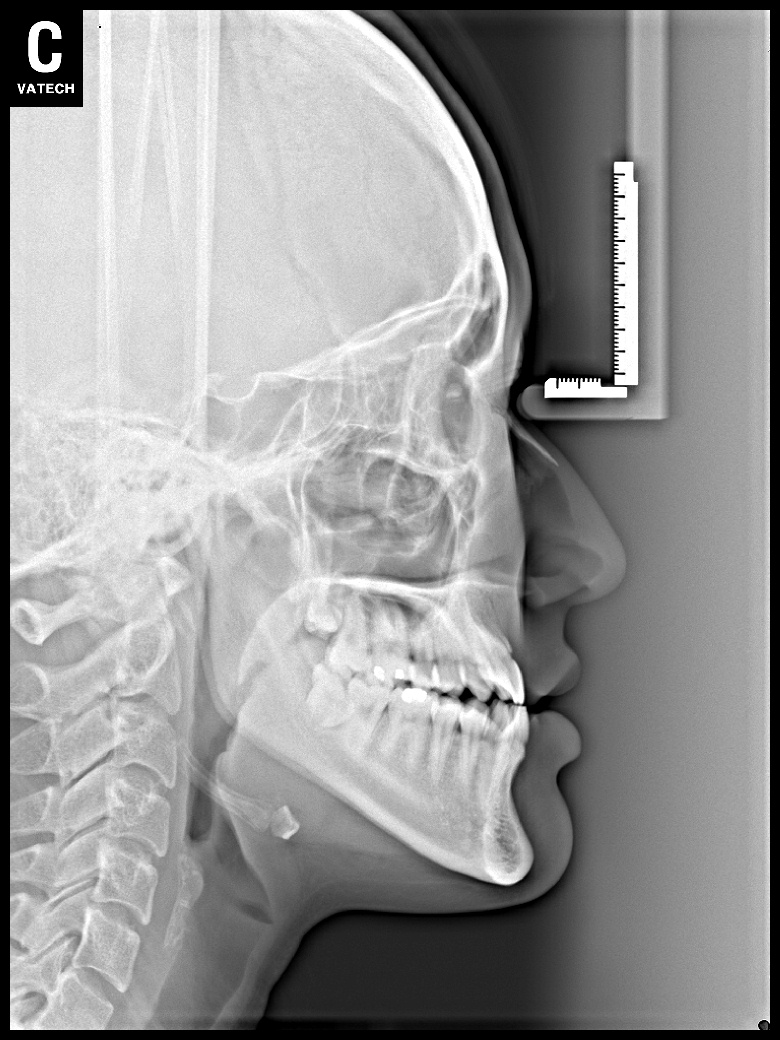

치료 전 사진입니다.